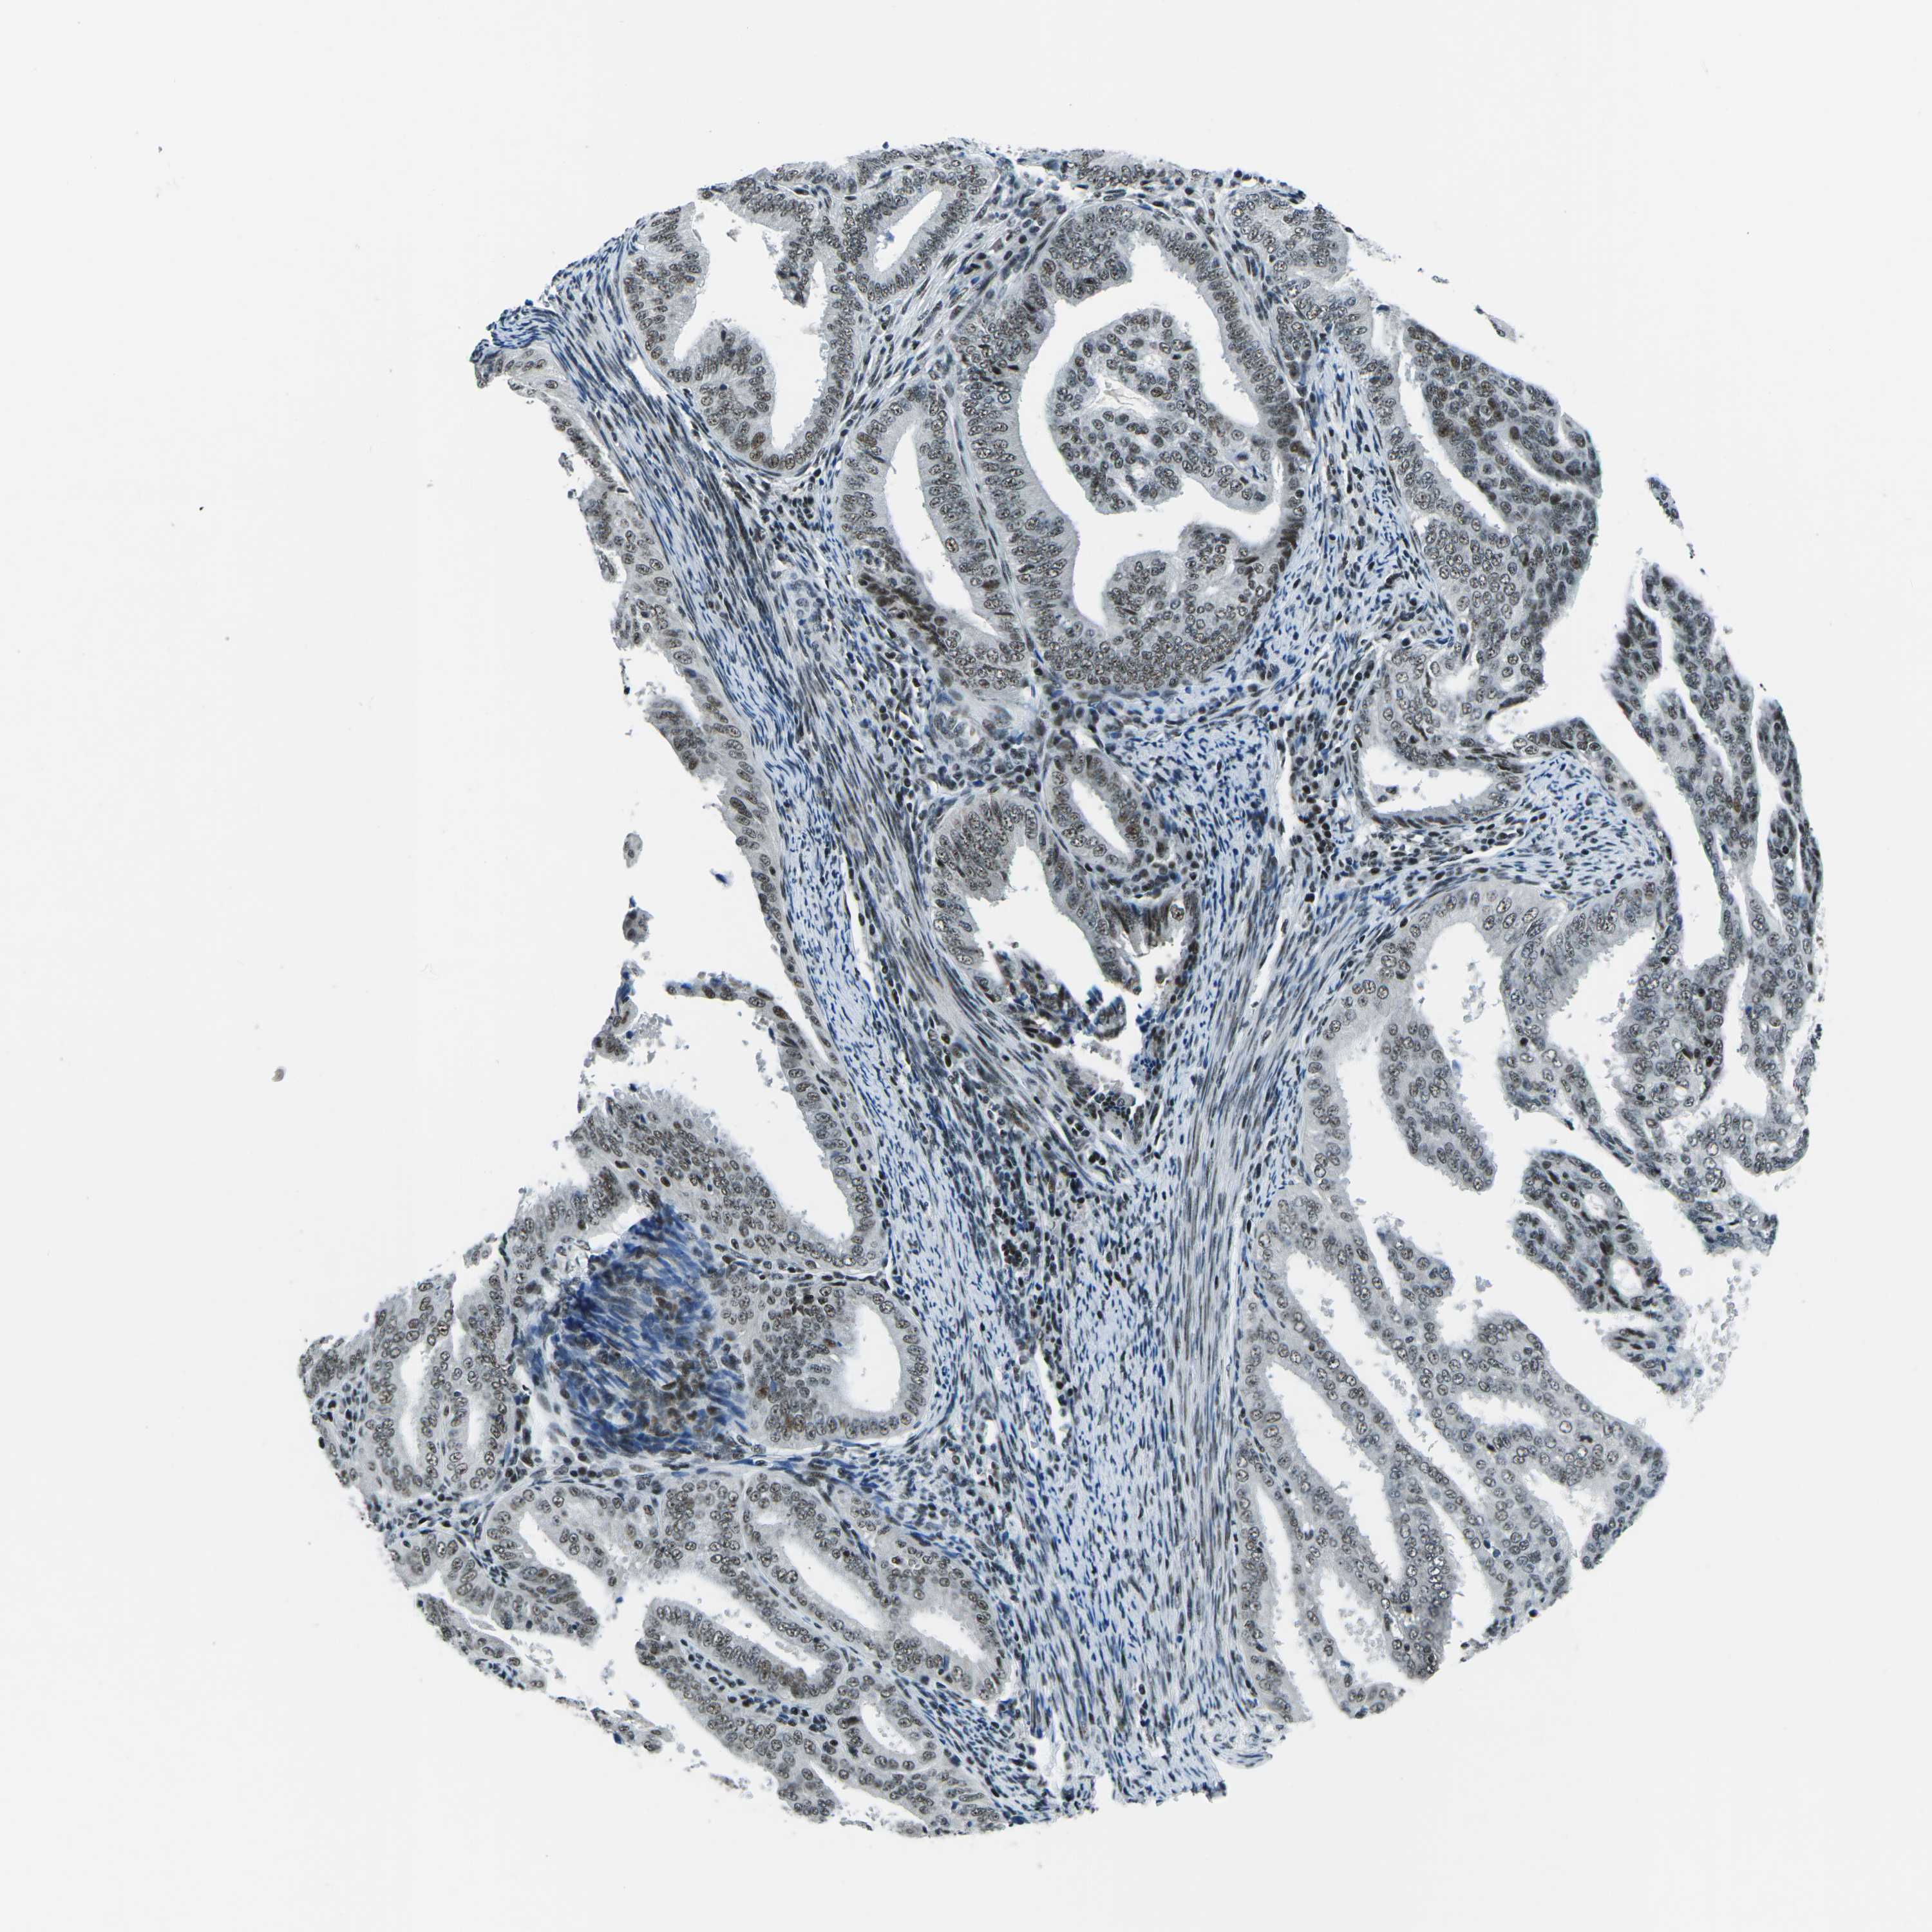

ENDOMETRIAL CANCER - Protein expressioni

A mouse-over function shows sample information and annotation data. Click on an image to view it in a full screen mode. Samples can be filtered based on level of antibody staining by selecting one or several of the following categories: high, medium, low and not detected. The assay and annotation is described here.

Note that samples used for immunohistochemistry by the Human Protein Atlas do not correspond to samples in the TCGA dataset.

Antibody stainingi

Antibody staining in the annotated cell types in the current human tissue is reported as not detected, low, medium, or high, based on conventional immunohistochemistry profiling in selected tissues. This score is based on the combination of the staining intensity and fraction of stained cells.

Each image is clickable and will lead to virtual microscopy that enables deeper exploration of all samples and also displays staining intensity scores, fraction scores and subcellular localization as well as patient and tissue information for each sample.

Antibody HPA019703

Antibody CAB016547

Staining

High

Medium

Low

Not detected

Intensity

Strong

Moderate

Weak

Negative

Quantity

>75%

75%-25%

<25%

None

Location

Nuclear

Cytoplasmic/membranous

Cytoplasmic/membranous,nuclear

Adenocarcinoma, NOS

Adenoma, NOS